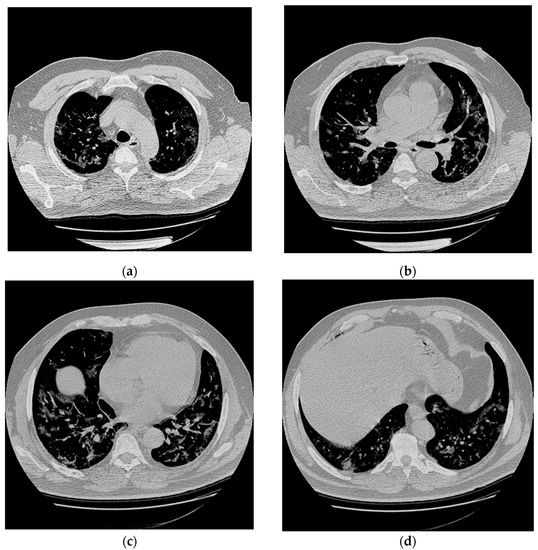

2.1. Hospital Phase